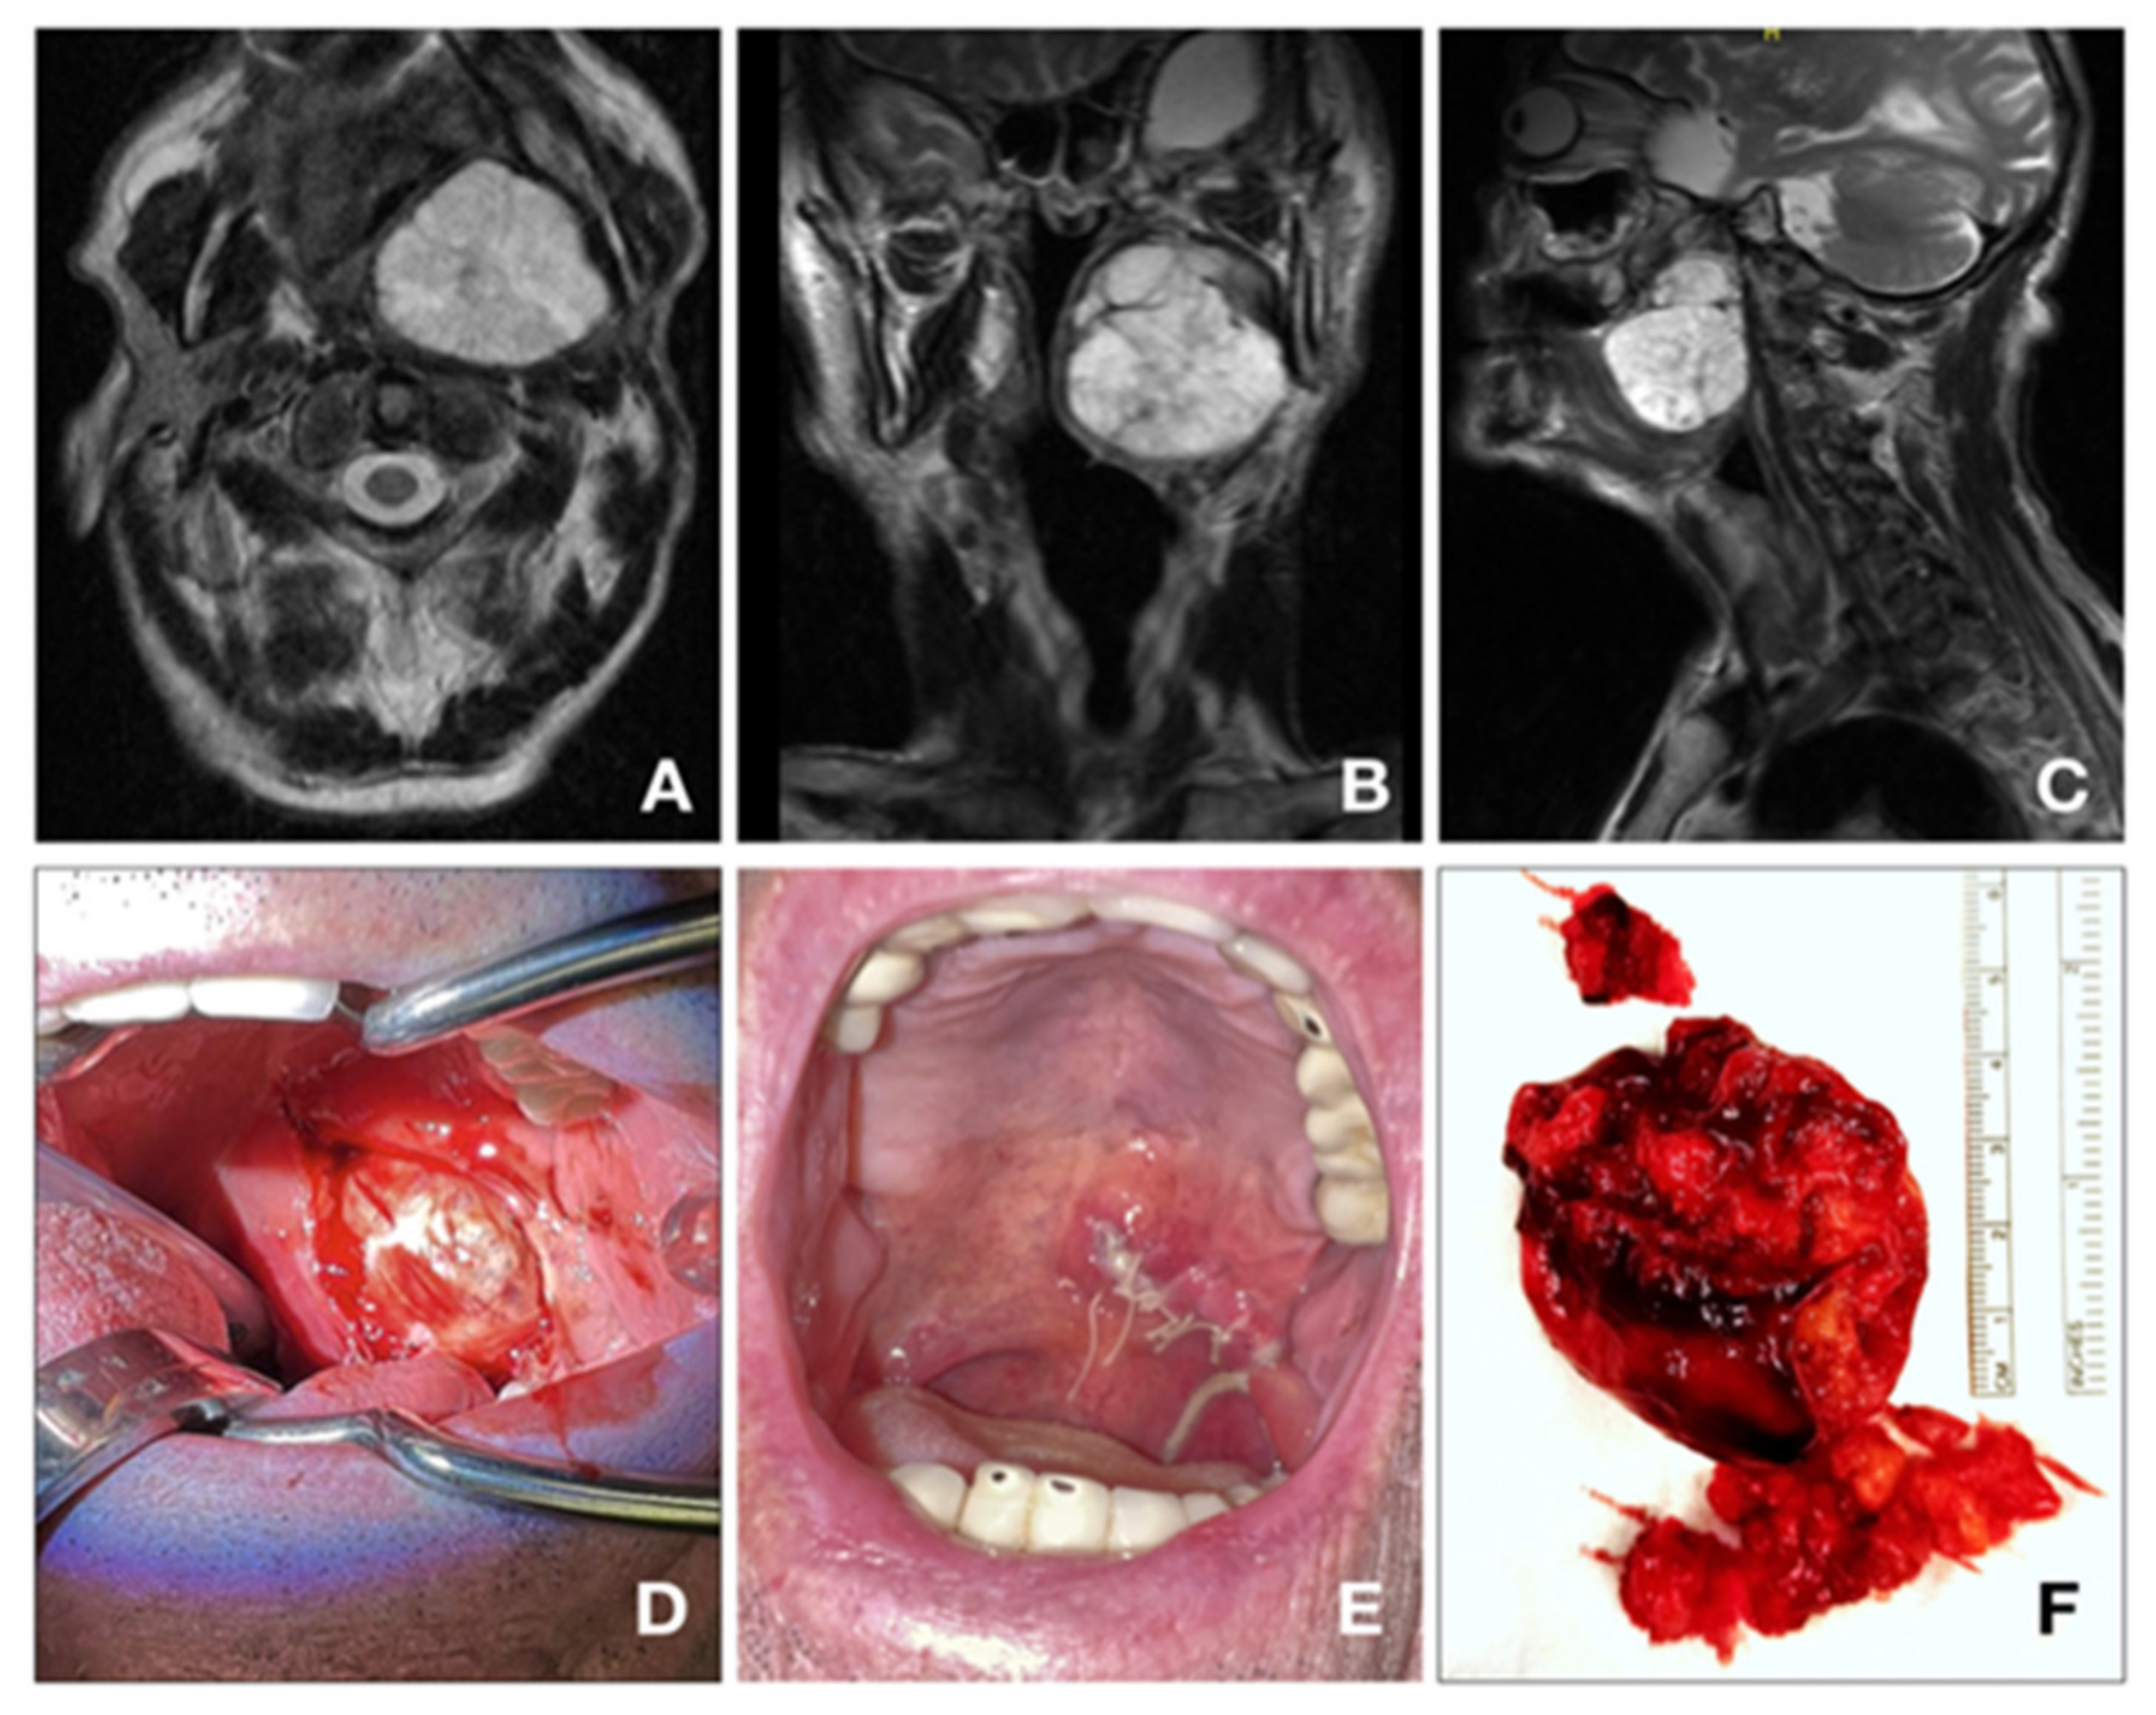

3.3. Surgery

3.4. Post-Operative Complications